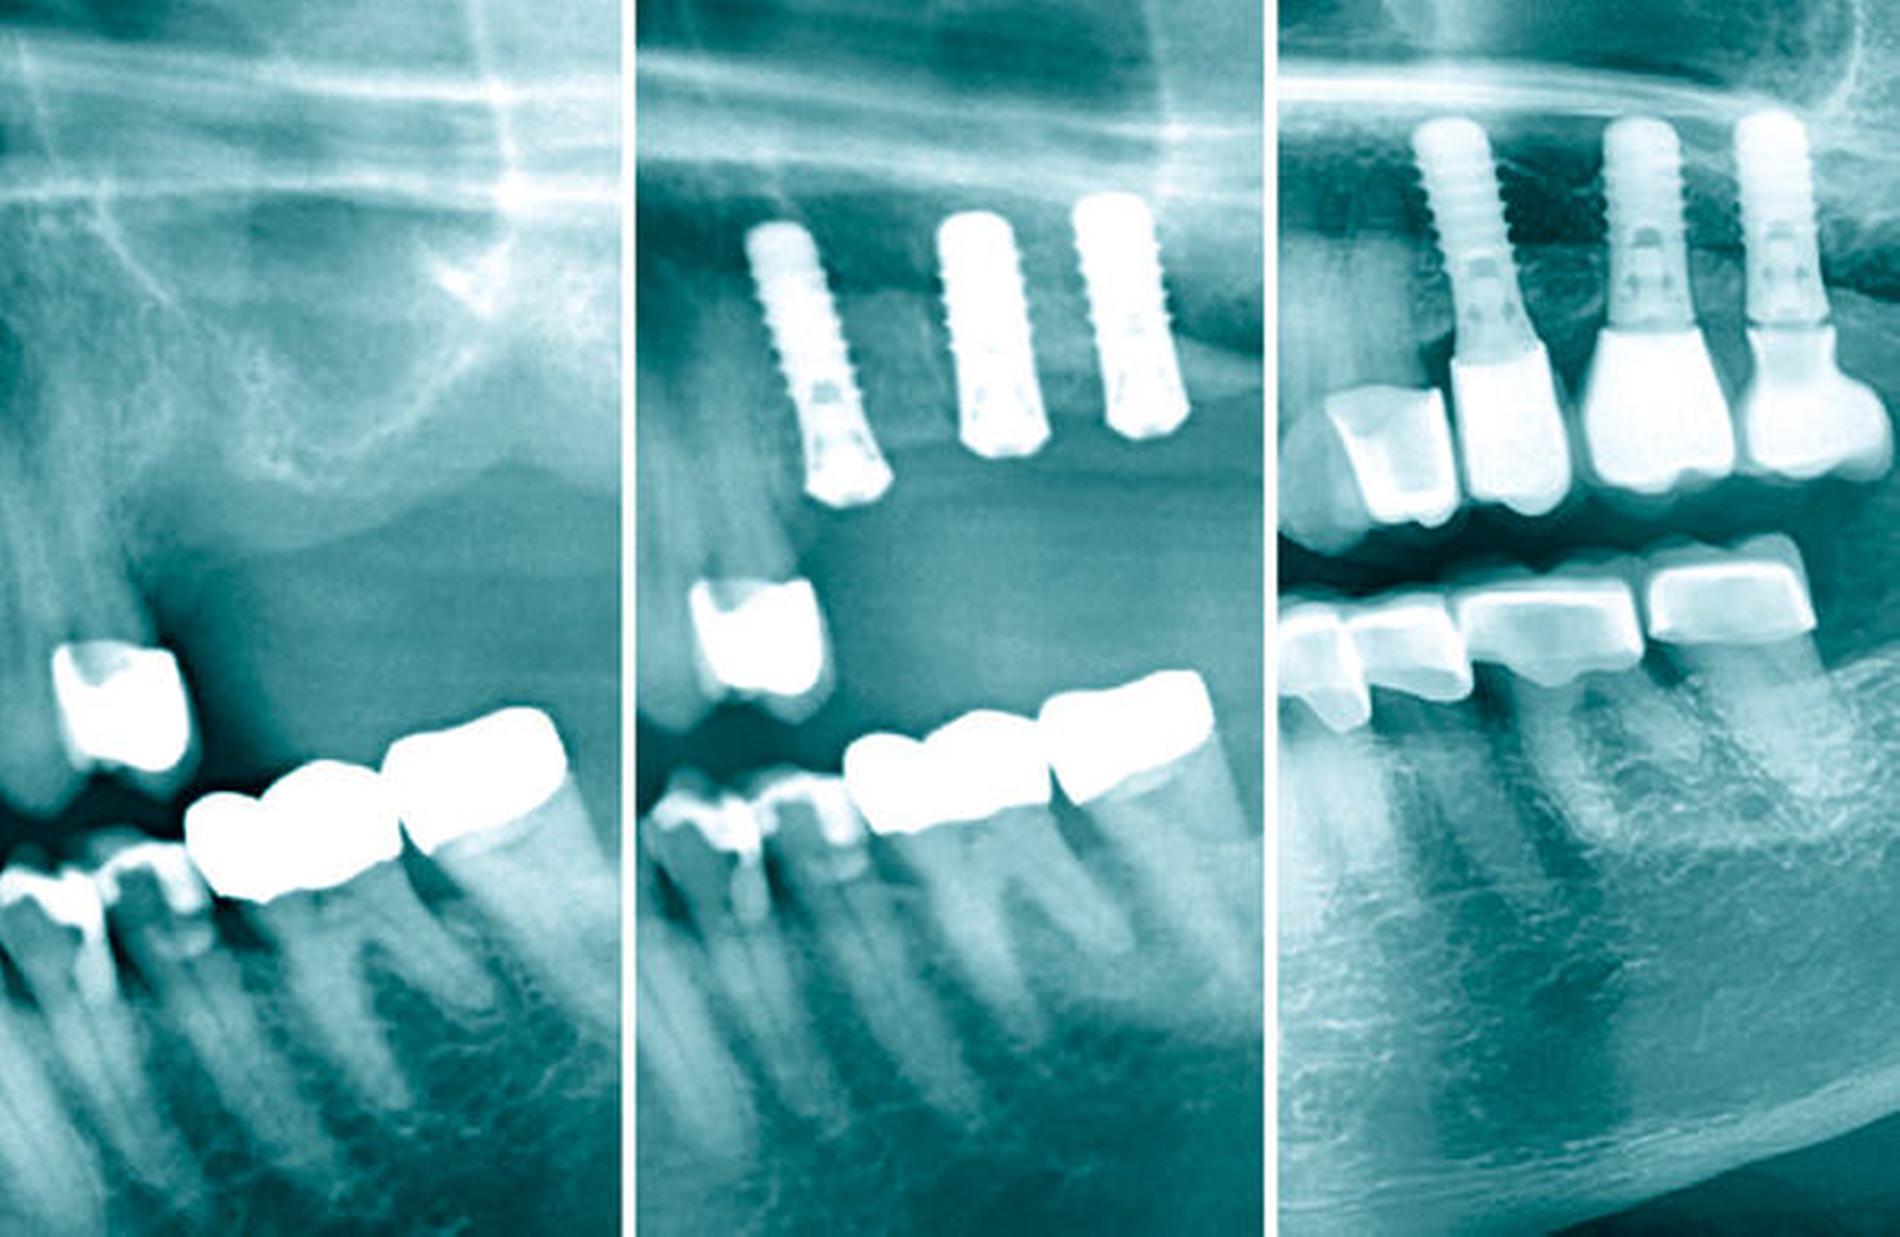

Mit diesen nadelförmigen Knochenstücken aus der Knochenpresse lässt sich selbst in Grenzfällen mit einer Restknochenhöhe im Bereich von 1 mm häufig eine zufriedenstellende Primärstabilität der Implantate erreichen, so dass bei der überwiegenden Mehrzahl der Operationen ein einzeitiges Vorgehen ermöglicht wird, was auch bei diesem Eingriff realisiert worden konnte. Es folgten die Insertion eines Implantats 4,1 x 10 mm (Straumann® Standard, Tissue Level) in Regio 25 und eines Implantats 4,8 x 10 mm (Straumann® Standard, Tissue Level) in Regio 26 (Straumann®, Basel, Schweiz) sowie ein Wundverschluss ohne Periostschlitzung und unter minimaler Spannung.

In den Abbildungen 6 bis 9 sind mehrere Fälle mit langem Beobachtungszeitraum dargestellt. Beachtenswert ist vor allem der zu beobachtende vollständige Umbau des Knochens inklusive der Ausbildung einer neuen Kompakta. Die augmentierten Bereiche sind nach wenigen Jahren nicht mehr als solche zu erkennen. Die Arbeit mit autologem Knochen ist insbesondere für die Patientengruppe interessant, die bevorzugt nach biologisch sicher verträglichen Behandlungen sucht. Dieser Trend nimmt unseren Beobachtungen nach stetig zu. n

In OPGs von Fällen, in denen rein autolog transplantiert wurde, fällt unter Umständen eine Sinterung des Knochens um die Implantatspitze auf. Eine frühe Belastung der Implantate kann diesem Vorgang entgegenwirken. Die Hauptbelastung beim Kauvorgang trägt bekannterweise der Knochen im koronalen Drittel des Implantats, der Druck lässt Richtung apikal immer mehr nach [Himmlová et al., 2004]. An der Implantatspitze erfährt der Knochen unter Umständen dann keinerlei Belastung mehr und atrophiert dementsprechend, was jedoch zu keiner Verschlechterung der Prognose führt. Betont werden muss, dass diese „Inaktivitätsatrophie“ unsere persönliche Hypothese ist. Auch in der Literatur konnte allerdings bisher kein negativer Effekt auf die Implantatüberlebensrate festgestellt werden [Chen et al., 2021]. Unsere Erfahrung zeigt, dass dieser Effekt ab einer Implantatlänge über 10 mm signifikant zunimmt, so dass wir inzwischen nur Implantate mit einer maximalen Länge von 10 mm verwenden.